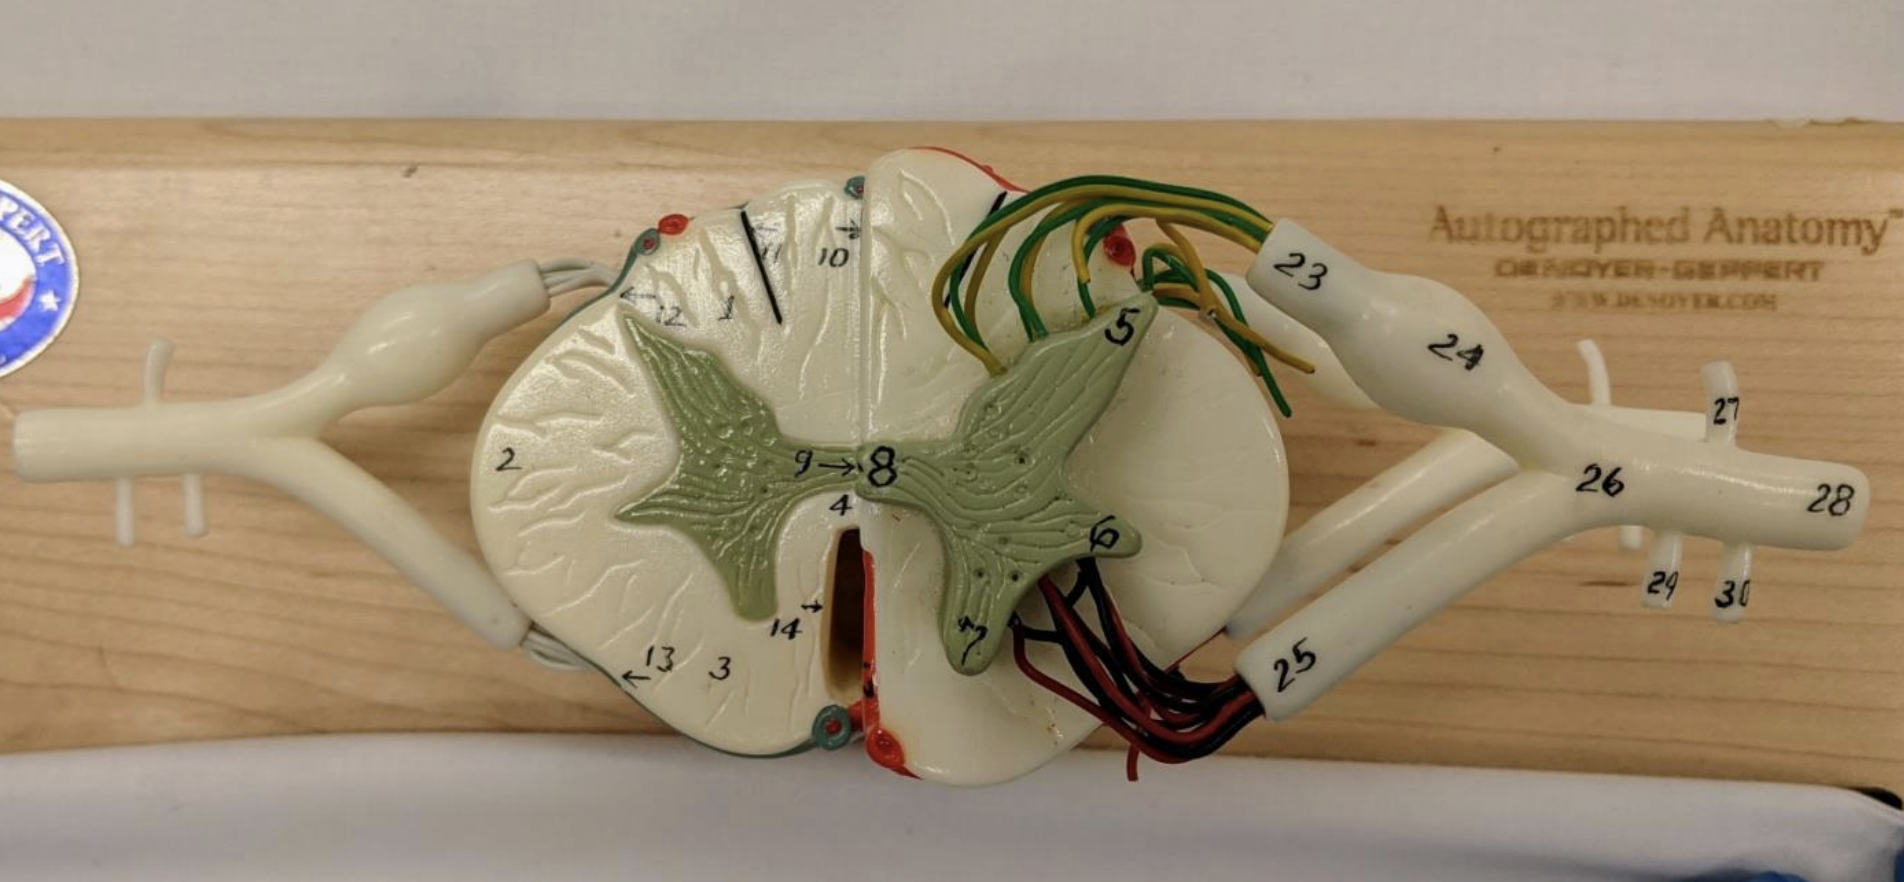

Ventral and dorsal rami

Rami communicantes

What do the ventral and dorsal rami innervate?

Dorsal: innervate back skin and muscle

Ventral: plexuses and thoracic nerves

Recurrent meningeal nerve

Supplies the facet joint, annulus fibrosus, vertebral ligaments, blood vessels and meninges